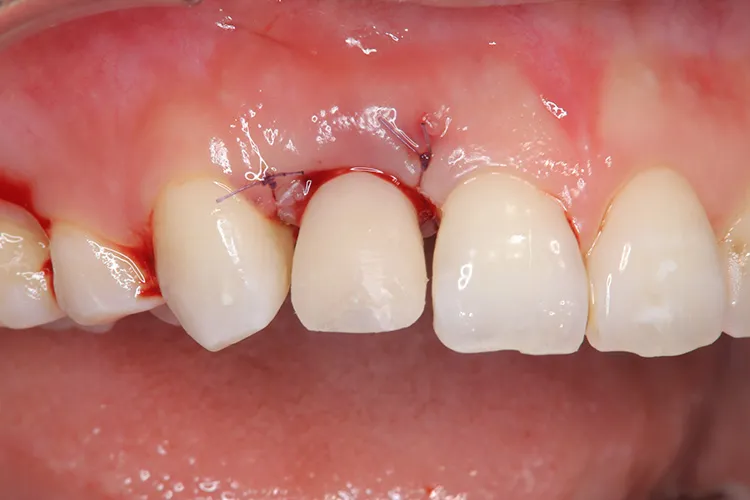

怪我で歯が折れてしまったケースです。前歯なので抜歯即時埋入で対応しました。即時で仮歯まで入れ、見た目の回復を行いました。その後歯肉が治りインプラントが安定したタイミングで最終の被せ物を装着しオペから3ヶ月で治療完了しました。